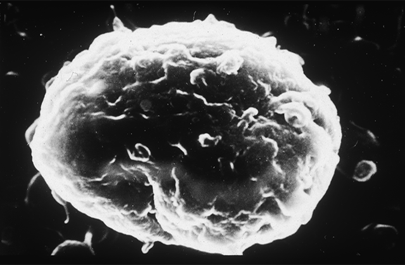

Le mélanome est une tumeur maligne qui se développe à partir des mélanocytes, les cellules de l'épiderme, qui produisent un pigment colorant la peau, la mélanine. La tumeur se développe d'abord à la surface de la peau avant de continuer en profondeur. Dans un quart des cas environ, le point de départ du mélanome est un grain de beauté (naevus) qui se transforme en cancer. C'est le plus rare des cancers de la peau mais aussi le plus grave, car il a tendance à se disséminer loin de la lésion initiale et à envahir d'autres organes : ce sont les métastases.

© Inserm/Dubertret, Louis